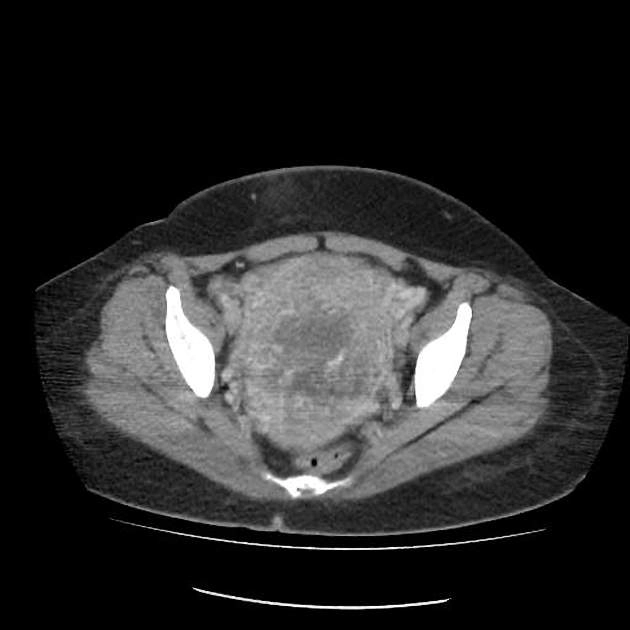

Thai trứng xâm lấn (Invasive mole)